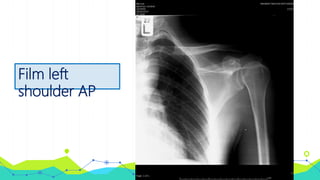

• Film left shoulder AP, left shoulder transcapular หลัง

closed reduction

Film left

shoulder AP